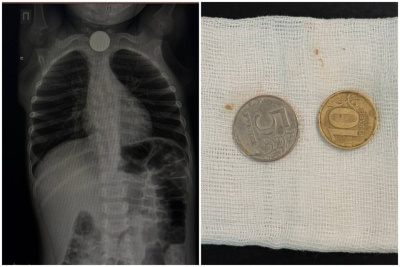

В Национальный центр медицины Якутии госпитализировали трехлетнего ребенка, проглотившего монеты номиналом пять и десять рублей. Инородные тела застряли в верхней трети пищевода, сообщает ЯСИА.

Мальчика беспокоили кашель и обильное слюнотечение. Экстренную операцию провела врач-эндоскопист, заведующая эндоскопическим отделением РБ № 1 – НЦМ Мария Еремеева.

«Родители обратились в больницу в тот же день, когда ребенок проглотил монеты. Инородные тела были обнаружены в верхней трети пищевода. Операция прошла успешно, сложностей при извлечении монет не возникло. После операции ребёнок в удовлетворительном состоянии остался под наблюдением в хирургическом отделении», — рассказала ЯСИА Мария Еремеева.